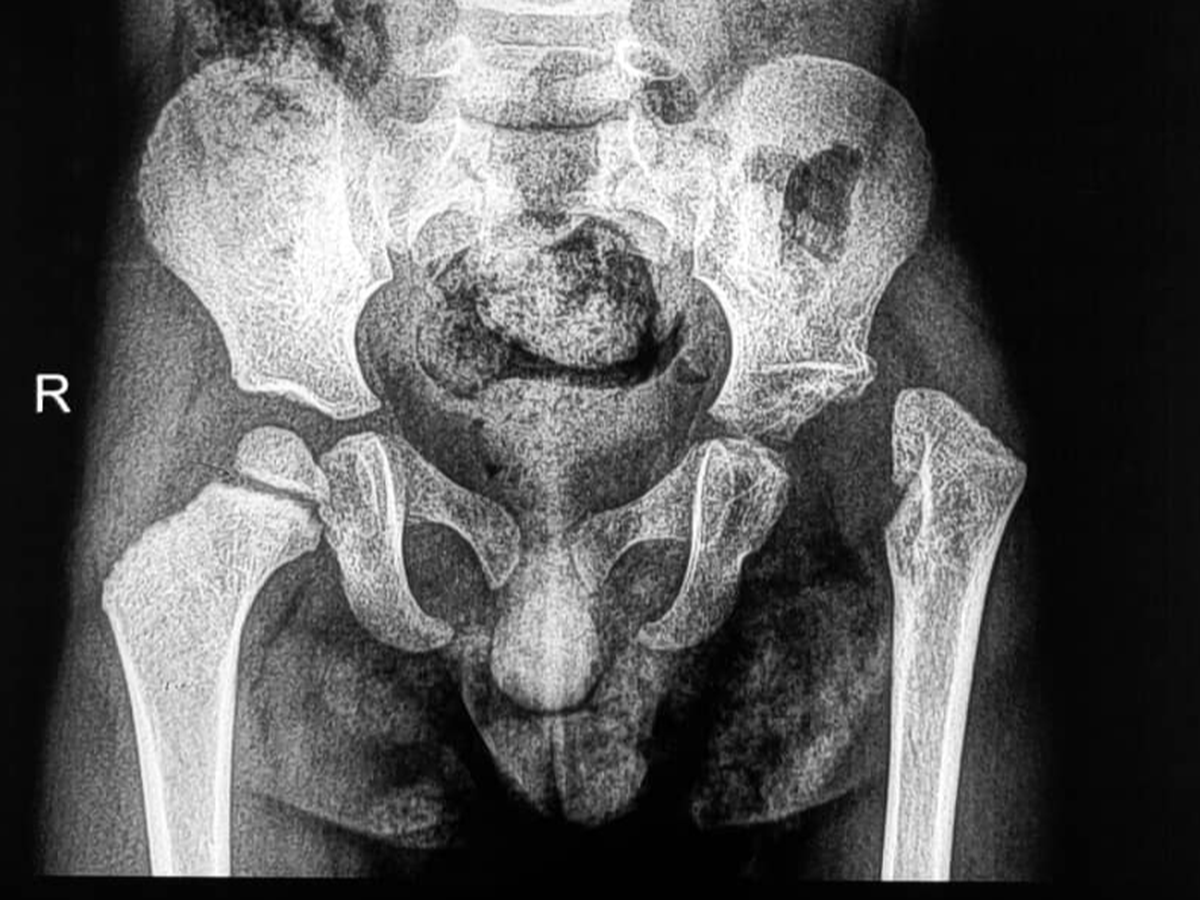

Das Kind / Mahd Mazen Mokhtar Ali, dreiundeinhalb Jahre alt, leidet unter dem Fehlen des linken Oberschenkelkopfes infolge von Folgen einer eitrigen Entzündung des linken Hüftgelenks. Dies hat zu einer Instabilität des Gelenks sowie zu einer Verkürzung der unteren Extremität geführt, bedingt durch das Fehlen der oberen Wachstumszone des Oberschenkelknochens.

الطفل / مهد مازن مختار علي والبالغ من العمر ثلاث سنوات ونصف يعاني من غياب لرأس عظمة الفخذ الأيسر ناتج عن عقابيل التهاب صديدي بمفصل الحق الأيسر مما نتج عنه عدم ثبات بالمفصل مع قصر بالطرف السفلي نتيجة غياب مركز النمو العلوي لعظمة الفخذ. والمريض يحتاج إلى جراحة ميكروسكوبية لنقل رأس عظمة الشظية مصحوبة بمركز النمو والممدودة بالأوعية الدموية، وتكلفة الجراحة حوالي 10000$، فقط عشرة آلاف دولار., وهو ما يعادل 8600 يورو تقريبا.